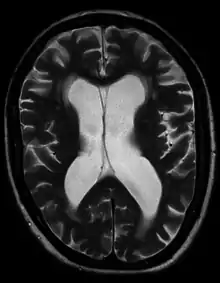

| Hydrocephalus as seen on a CT scan of the brain. The black areas in the middle of the brain (the lateral ventricles) are abnormally large and filled with fluid. | |